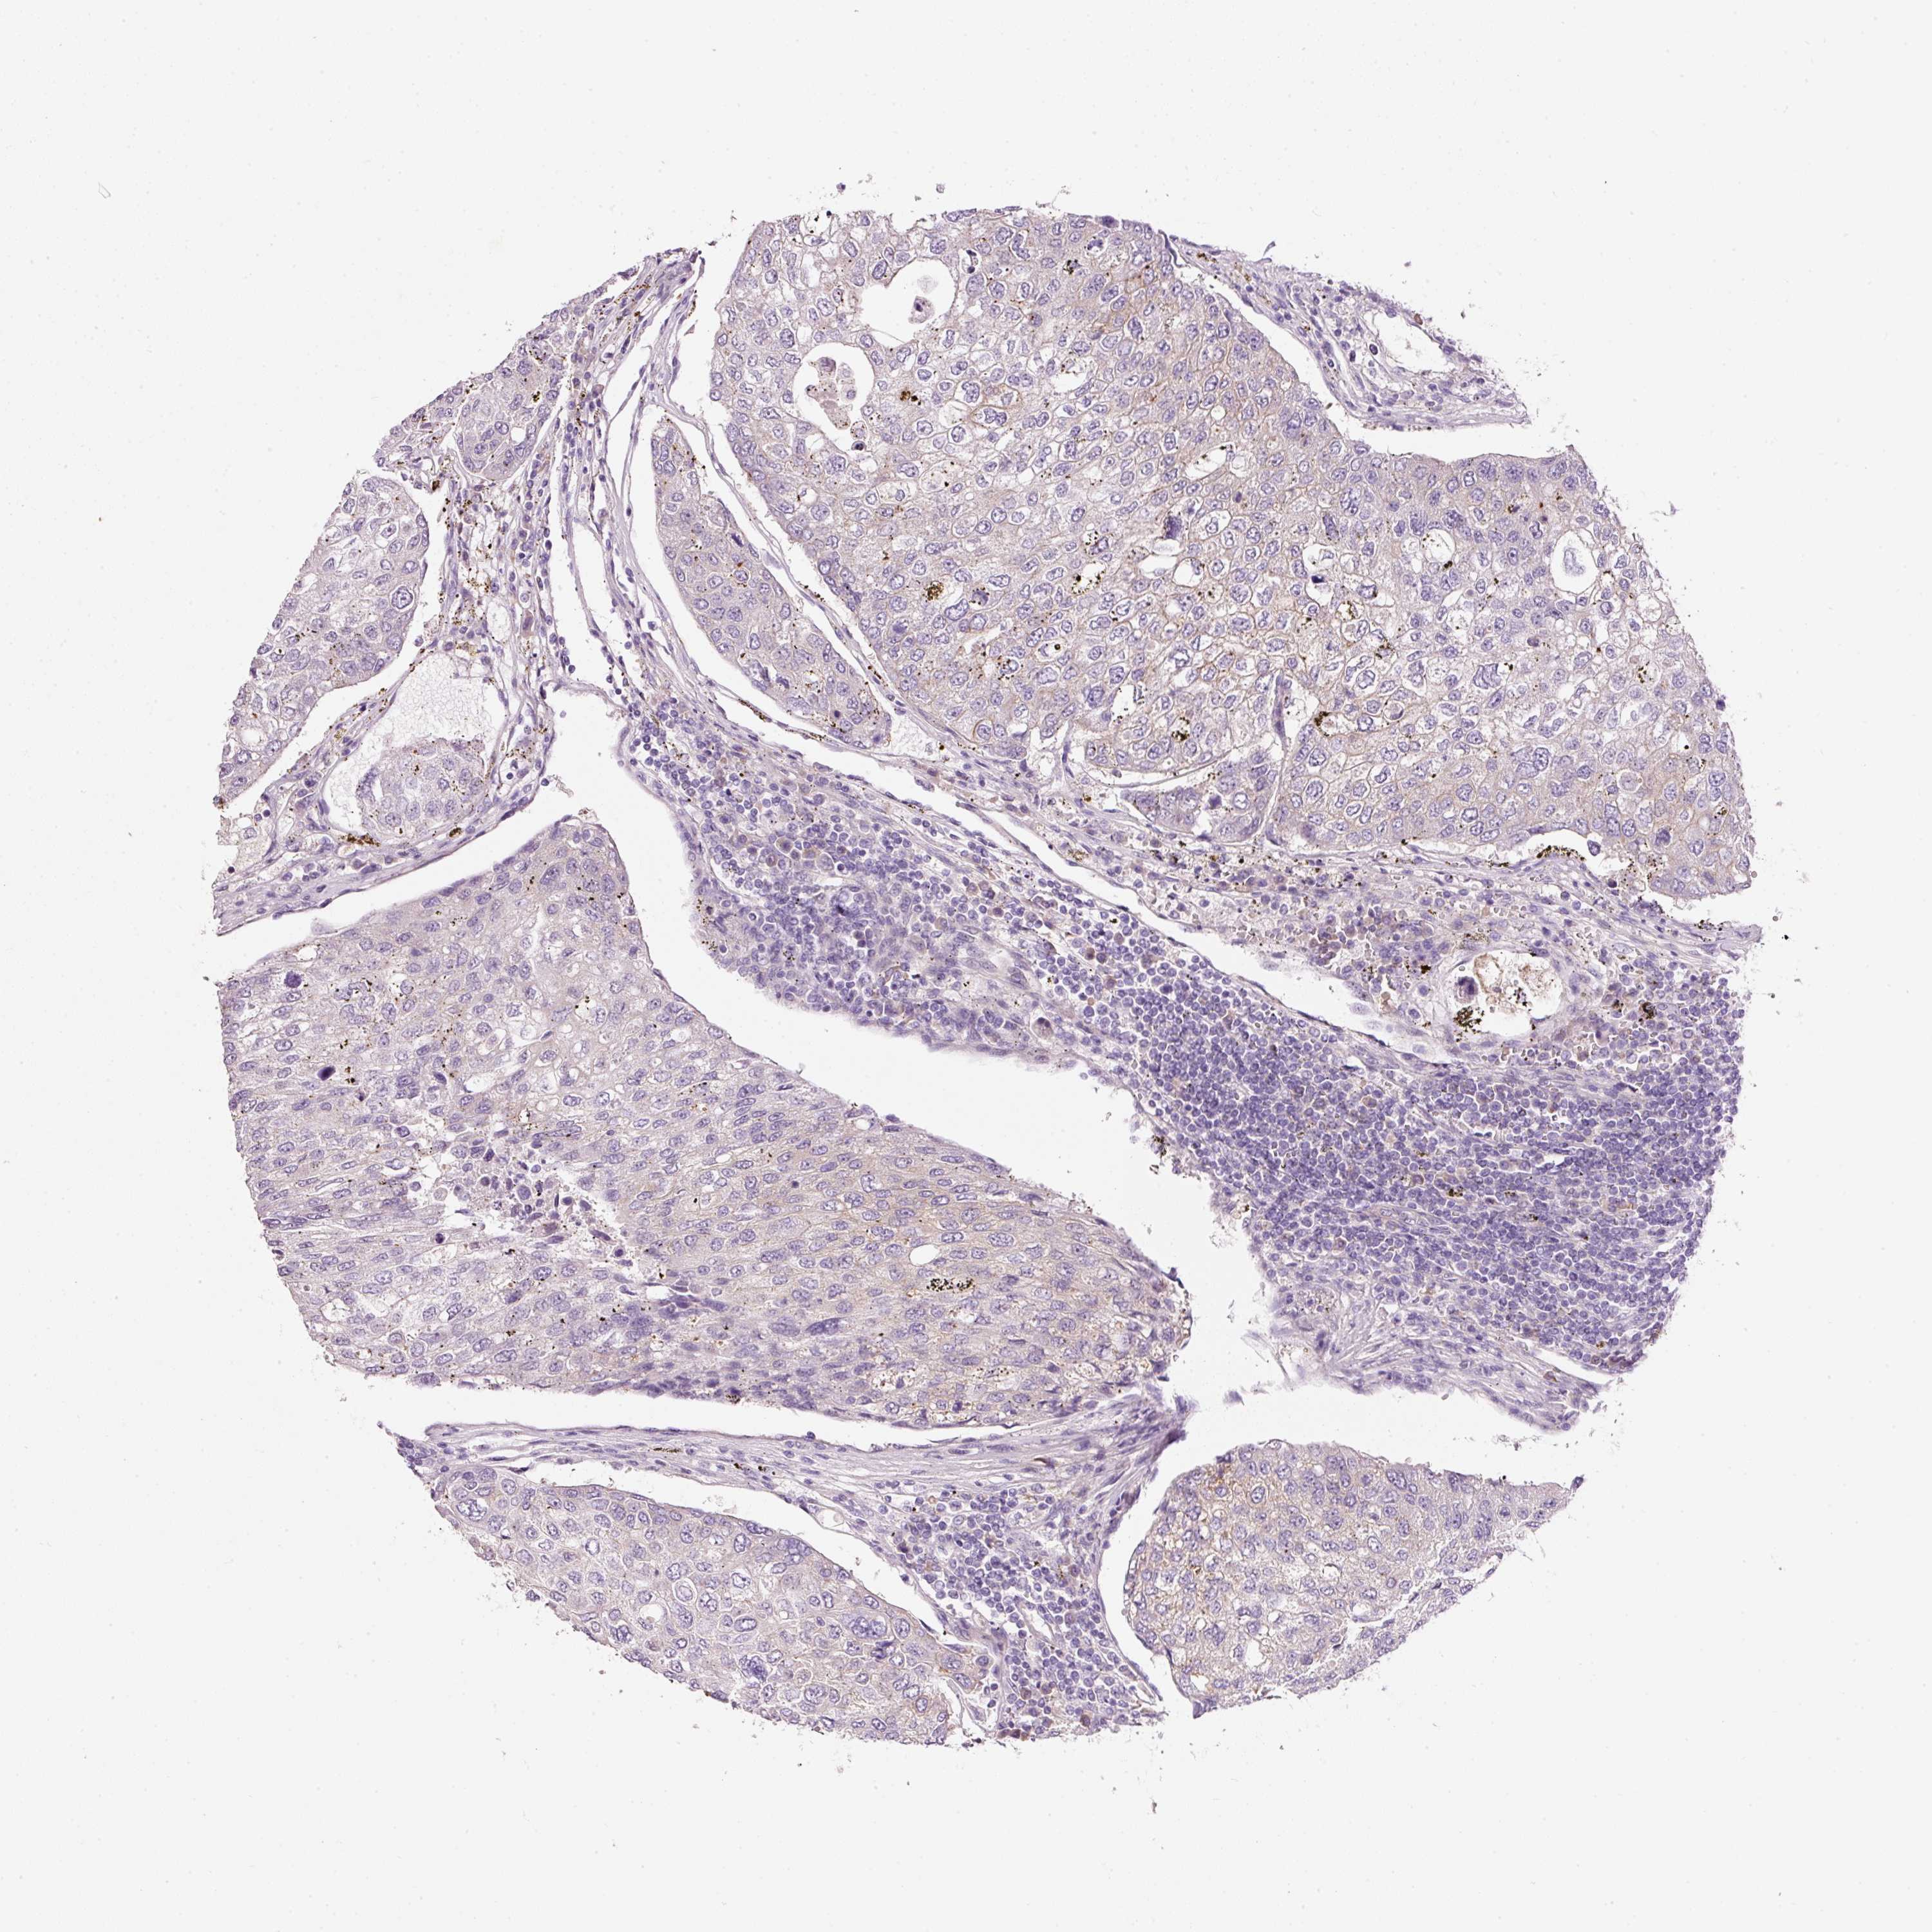

UROTHELIAL CANCER - Protein expressioni

A mouse-over function shows sample information and annotation data. Click on an image to view it in a full screen mode. Samples can be filtered based on level of antibody staining by selecting one or several of the following categories: high, medium, low and not detected. The assay and annotation is described here.

Antibody stainingi

Antibody staining in the annotated cell types in the current human tissue is reported as not detected, low, medium, or high, based on conventional immunohistochemistry profiling in selected tissues. This score is based on the combination of the staining intensity and fraction of stained cells.

Each image is clickable and will lead to virtual microscopy that enables deeper exploration of all samples and also displays staining intensity scores, fraction scores and subcellular localization as well as patient and tissue information for each sample.

Antibody HPA047368

Antibody CAB004577

Staining

High

Medium

Low

Not detected

Intensity

Strong

Moderate

Weak

Negative

Quantity

>75%

75%-25%

<25%

None

Location

Nuclear

Cytoplasmic/membranous

Cytoplasmic/membranous,nuclear

Urothelial carcinoma, Low grade